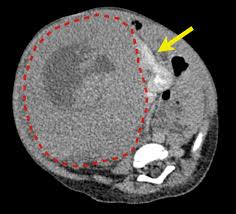

Kidney Tumor On Ct Scan. He also sent me for ct scan to get a clearer view turns out they spotted something on a kidney. Some patients however may need a biopsy.

He also sent me for ct scan to get a clearer view turns out they spotted something on a kidney. Typically these are detected incidentally in other words the patient has a scan for an unrelated problem and a tumor in the kidney is found. It this were indeed a kidney cancer it would be nearly impossible for it to have spread at that size.

Not all growths on. Kidney tumor contained within the kidney small kidney tumor 4cm increasingly we are detecting these small kidney tumors due to the increased use of ultrasound ct scan and mri. It this were indeed a kidney cancer it would be nearly impossible for it to have spread at that size. On imaging they have a variety of radiographic appearances from solid and.